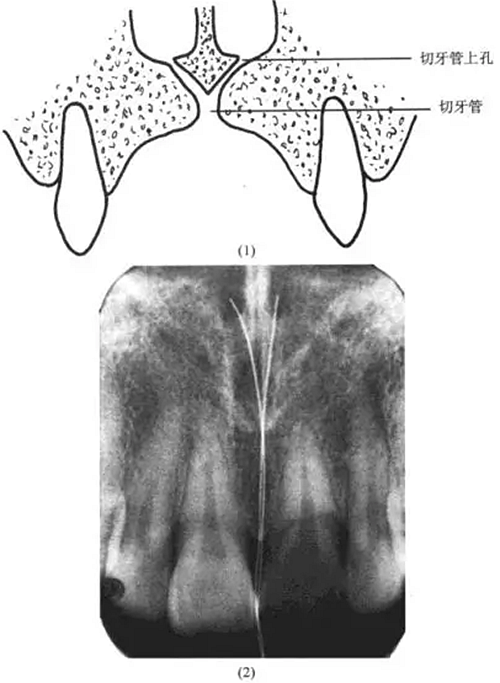

理由:解剖復習

切牙孔:在給片上常表現(xiàn)為一界限清楚的圓形、卵圓形密度較低影像,根尖片上切牙孔的位置可位于中切牙牙根之間,靠近牙槽嵴或在根尖平面。

切牙管:終于切牙孔,可見于中切牙的根尖片上。

切牙管上孔:共2個,位于鼻前唇底,與鼻中隔鄰接,根尖片上切牙管上孔的影像可能投射到任何切牙的根端,因而有時可誤認為根尖周病變(圖13-5)

上述病例的診斷可據(jù)此及牙髓活力存在而確診。